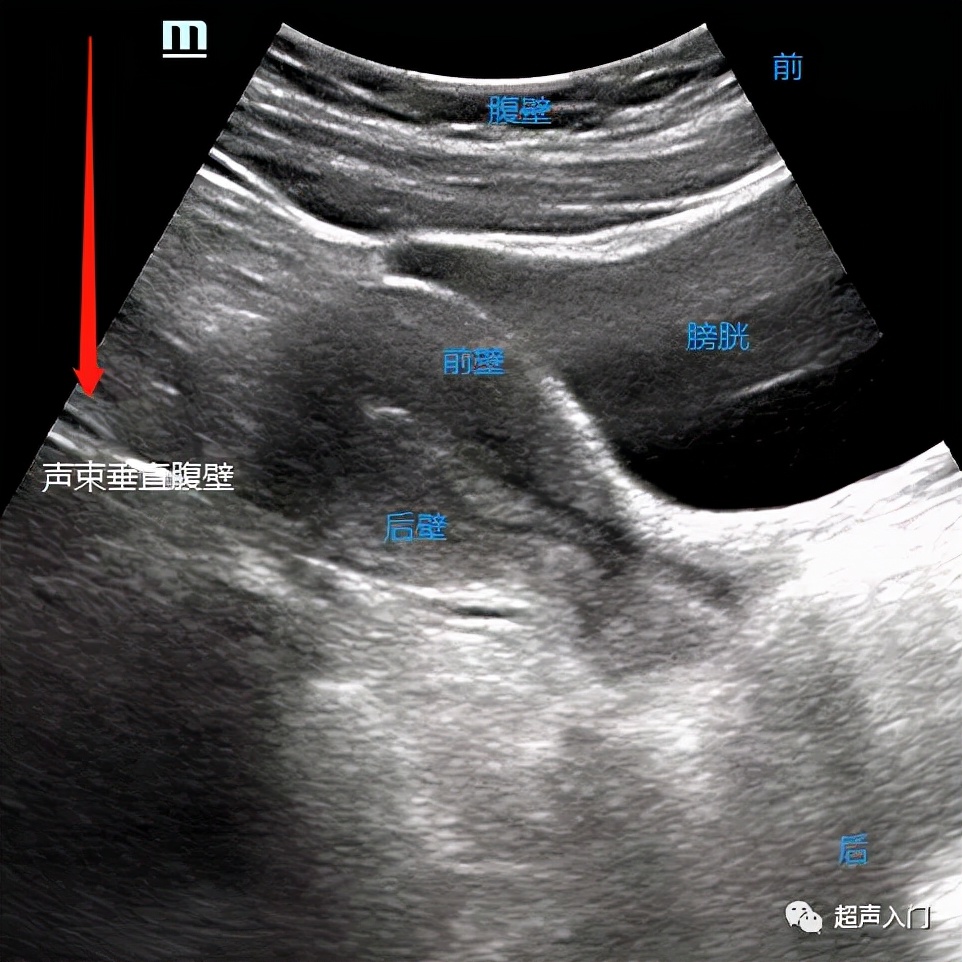

首先我们一起来了解经腹部超声看子宫如何区分前后。当宫体向前(腹壁侧)倾向的时候,我们就说此刻子宫为前位,同理,靠前方的子宫壁,也就称为前壁,子宫壁距离人体背侧近的时候为后壁。

所以经腹部看的超声不管是前平后位子宫,靠近腹侧的子宫壁就称为前壁。